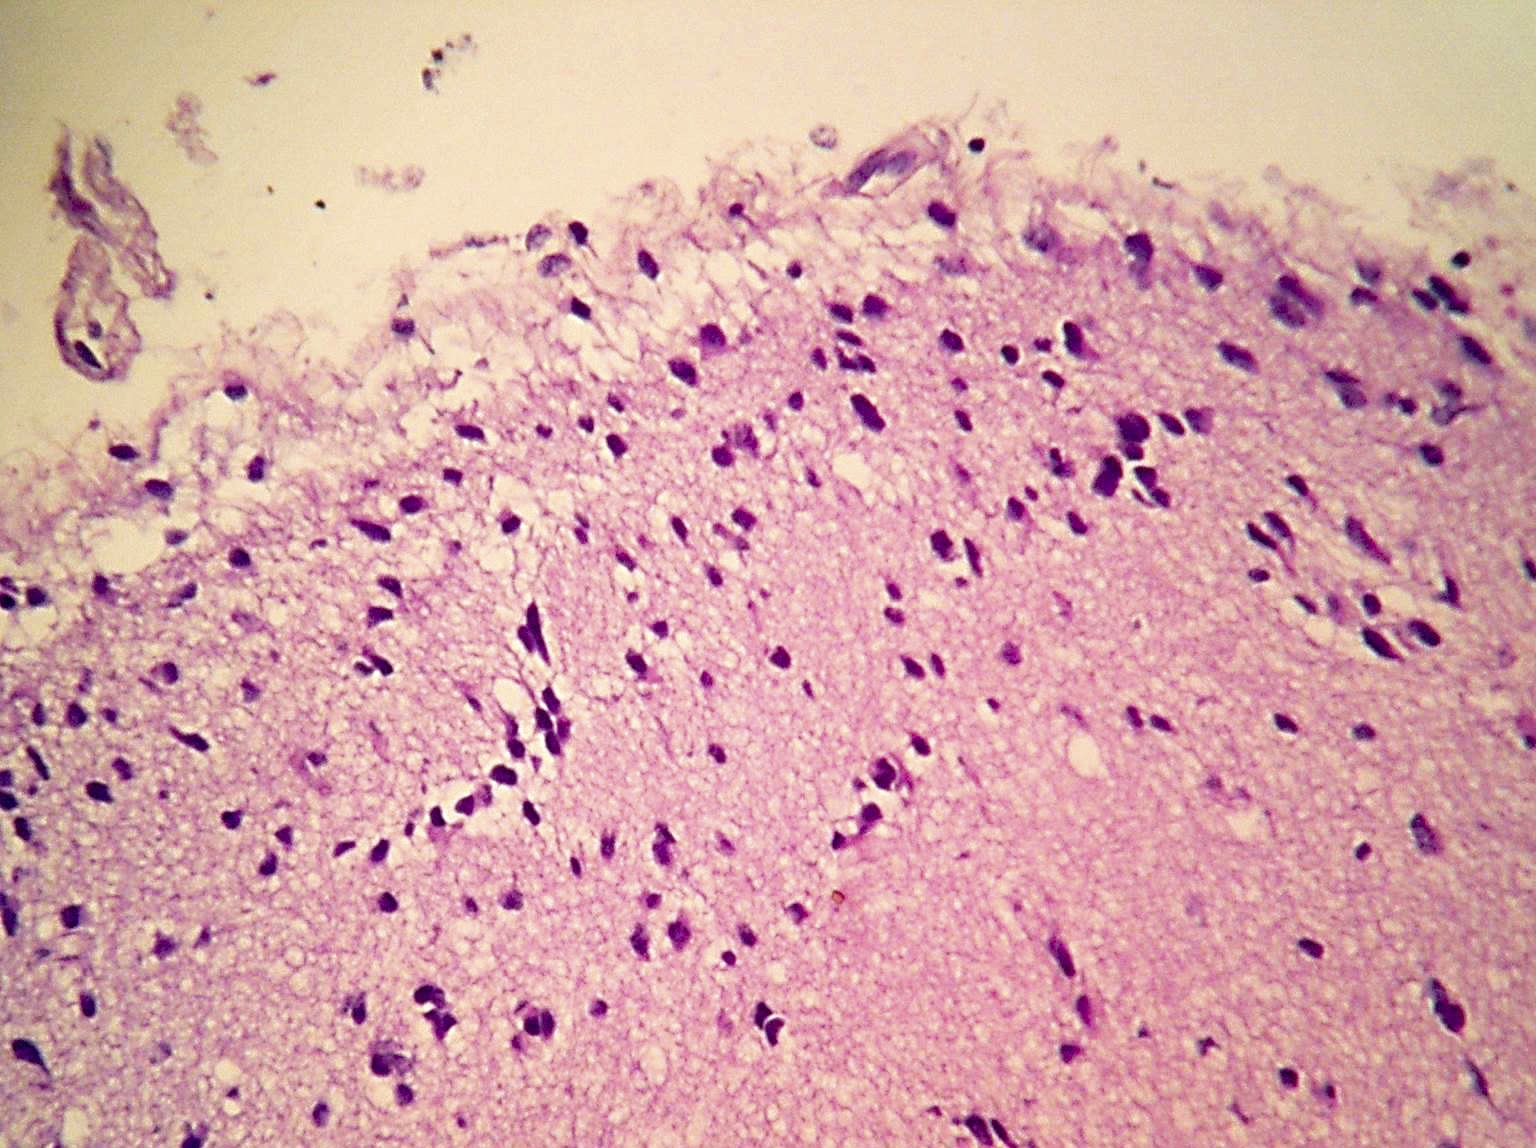

Microscopic (histologic) description

- Diffusely infiltrating tumor cells with oval to elongated astrocytic nuclei and varying appearance of tumor cytoplasm and fibrillar glial processes (Acta Neuropathol 2015;129:789)

- At the periphery, tumor cells may infiltrate in a diffuse single cell pattern, often with entrapped neurons and axons

- Cellular morphology is variable, even within a single tumor

- Commonly there is a mix of cells with elongated nuclei and fine fibrillar processes, cells with eccentric nuclei and glassy eosinophilic cytoplasm (gemistocytes), larger pleomorphic cells and small cells with scant cytoplasm

- May show oligodendroglioma-like areas

- Myxoid background and microcyst formation may be present

- Variable mitotic activity, cellularity and nuclear atypia depending on CNS WHO grade

- In small biopsy specimens, the presence of 1 mitosis may be sufficient for a CNS WHO grade 3 diagnosis, while the presence of a few mitotic figures in a large resection would not be sufficient for grade 3 designation (Acta Neuropathol 2020;139:603)

- Presence of necrosis or microvascular proliferation would be consistent with a CNS WHO grade 4 designation

Microscopic (histologic) images

Contributed by Eman Abdelzaher, M.D., Ph.D., John DeWitt, M.D., Ph.D. and Meaghan Morris, M.D., Ph.D.